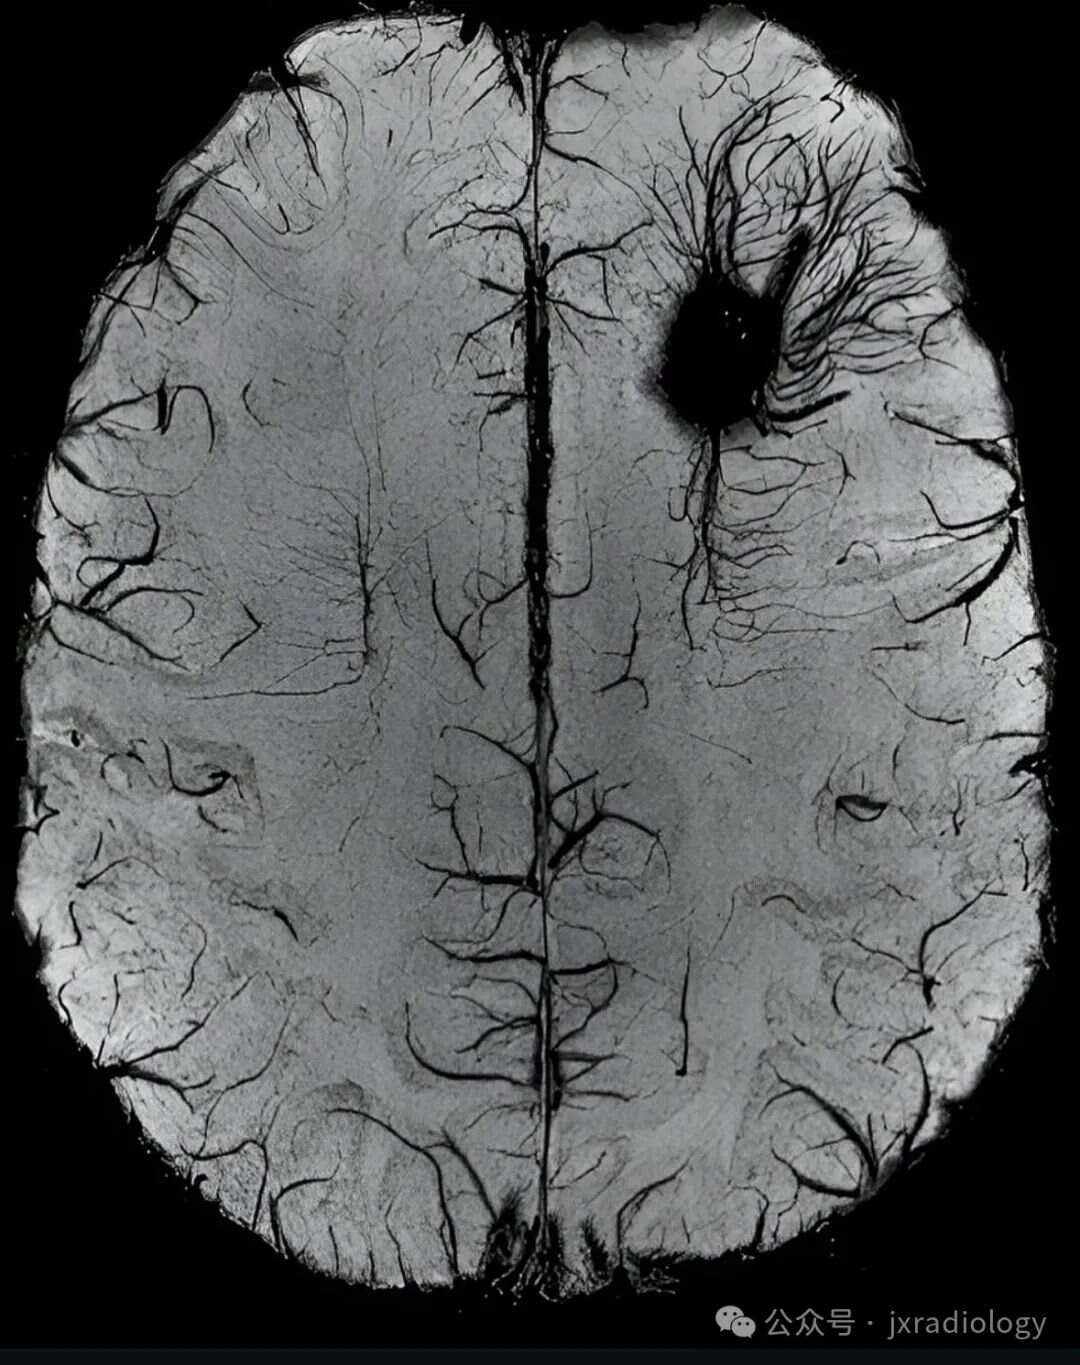

2、脑血管病的早期症状因病因不同而有所差异,主要分为以下两类一先天性血管病变的早期表现部分由动脉瘤血管畸形等先天性因素引发的脑血管病,早期可能无明显症状,但部分患者会出现以下表现1偶发或剧烈头痛头痛可能是早期唯一信号,尤其是突然发作的剧烈头痛需警惕2癫痫发作血管畸形可能。

4、脑血管痉挛的早期症状可分为神经系统症状眼部症状及其他伴随症状,具体表现如下一神经系统症状 头痛多为剧烈搏动性头痛,可单侧或全头分布,常由脑血管痉挛导致脑供血不足颅内血管张力改变引发蛛网膜下腔出血后约80%的患者会出现此症状,且程度严重,影响日常生活有脑血管病史者若出现不明。

8、脑血管病的症状因病变位置和严重程度而异,常见表现如下1 突然出现的头痛头痛是脑血管病的常见症状,但需与高血压偏头痛等鉴别若头痛突然加重,或伴随呕吐意识不清,需高度警惕脑血管病可能2 面部手臂或腿部麻木或无力脑血管病变导致脑部供血不足,可能引发单侧或双侧神经功能障碍,表现为。